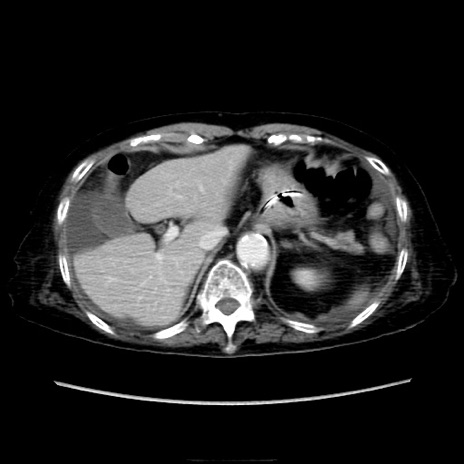

症例40(横断像)

【症例】90歳代女性

【主訴】腹痛・嘔吐

【現病歴】 食欲低下、嘔吐があり昨日他院受診。肺炎と診断され入院となる。入院後より腹部全体に圧痛あり。胃管留置され経過みていたが、症状持続するため、

当院転院となる。

【既往歴】胸椎圧迫骨折、胆石症

【身体所見】腹部:中央に激痛あり、圧痛あり、反跳痛不明

【データ】WBC 17100、CRP 18.82

横断像